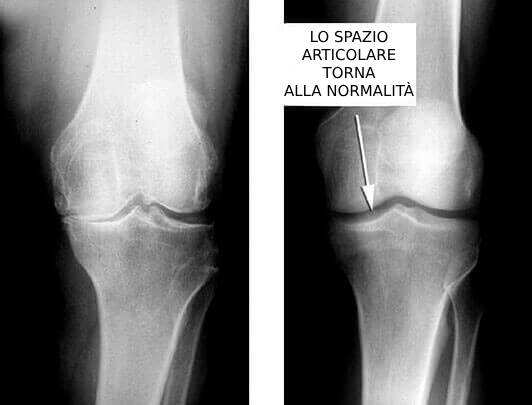

In questa radiografia voglio mostrarvi l'effetto del rimedio.